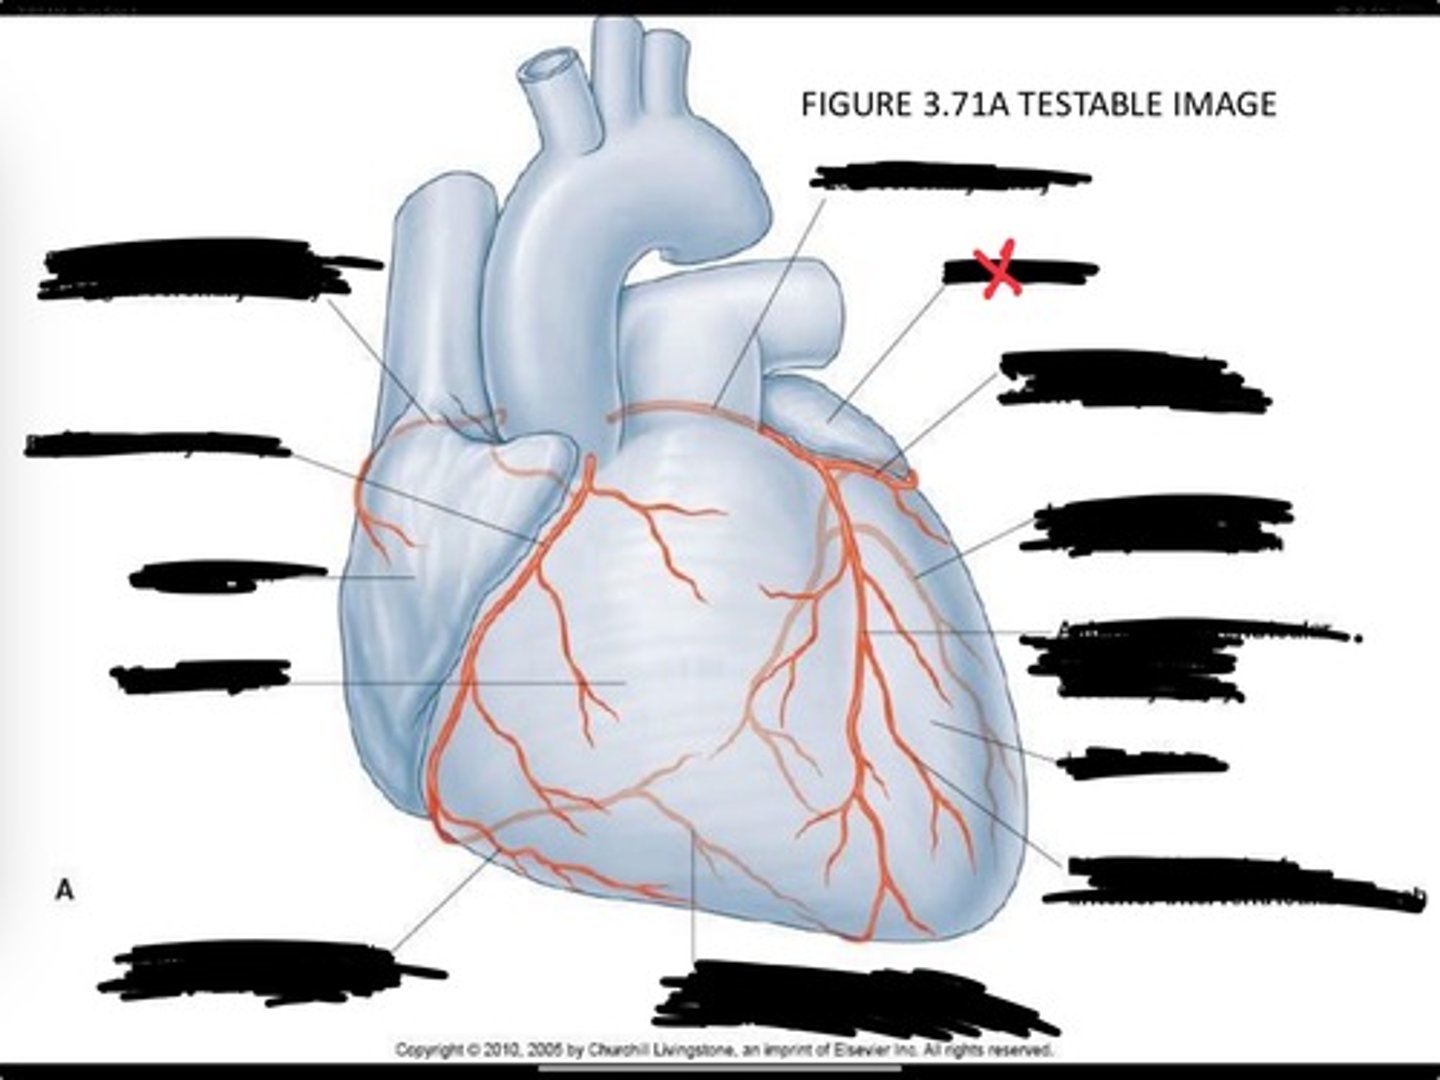

Posterior interventricular branch of right coronary artery

Right arginal branch of coronary artery

Right ventricle

Right atrium

Right coronary artery

Sinu-atrial nodal branch of right coronary artery

Left coronary artery

Left auricle

Circumflex branch of coronary artery